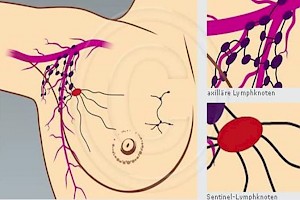

Die früher praktizierte komplette Ausräumung axilliäre Lymphknoten in der Therapie des Mammakarzinoms ist in erster Linie als diagnostisches Verfahren zur Abklärung der Frage zu verstehen, ob überhaupt und wenn ja,in welchem Ausmaß eine lymphogene Tumormetastasierung vorliegt. Bei den Patienten ohne nachweisbare Lymphknoten-Metastasen ("nodal-negative" Patienten) war diese Maßnahme ohne Einfluss auf den Erfolg der Tumortherapie, aber mit unvermeidbaren, die Lebensqualität beeinträchtigenden Nebenwirkungen verbunden. Rund 30 Prozent der betroffenen Frauen entwickeln nach der Ausräumung der axilliäre Lymphknoten ein behandlungspflichtiges Armlymphödem Bei der SLN-Methode sind es nur 5 Prozent.

Abb. 1

Abb. 1

Ein Lymphödem (Abb.1) entsteht durch eine Schädigung der Armlymphgefäße im Armwurzelbereich mit dadurch bedingter Störung im Lymphabfluss infolge operativer Entfernung oder radiogener Fibrosierung von axilliären oder klavikulären Lymphknoten. Lymphödeme bei Mammakarzinom können Arm-, Hand-, zugehörige Brustwand und Brustdrüse betreffen. Das Lymphödem manifestiert sich meist sofort nach der Operation, es kann jedoch auch infolge Narbenschrumpfung erst Monate bis Jahre später auftreten. Dies wird besonders nach einer Strahlentherapie beobachtet.

Der Sentinel-Lymph-Node (SLN), der auch Wächterlymphknoten genannt wird, ist der erste Lymphknoten, der im lymphatischen Abstromgebiet eines Tumors liegt. (Abb.2 rechts unten)

Damit ist dieser der Ort mit der wahrscheinlichsten Metastasierung.

Hat der SLN keine Metastasen, so ist die Wahrscheinlichkeit bei 95-97%, dass die anderen Lymphknoten auch tumorfrei sind.